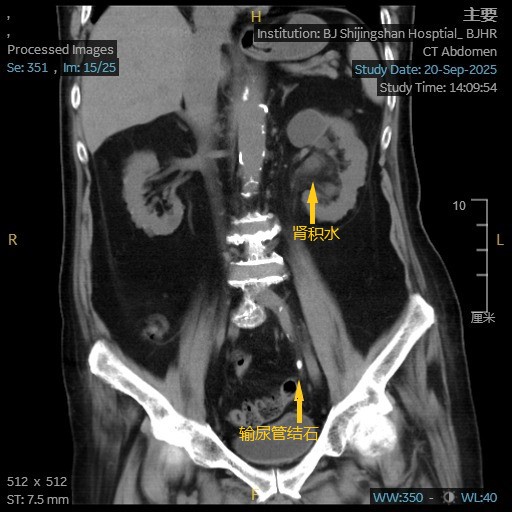

3周前,王爷爷突发左下腹剧痛,在外院确诊为“左侧输尿管下段结石”。然而,94岁高龄合并心肺功能差,麻醉风险犹如悬顶之剑,手术被迫暂缓。尝试体外碎石后,疼痛仍反复发作,老人被折磨得夜不能寐。

一周前,家属带着最后希望来到我院泌尿外科。更棘手的问题接踵而至——术前检查发现王爷爷左腿静脉存在血栓,直接手术可能导致致命肺栓塞!危急关头,泌尿外科立即启动多学科协作机制。心胸血管外科厉胜副主任医师火速会诊,当机立断:“放置下腔静脉滤网,为手术兜底!”24小时内,这颗“定时炸弹”被成功拦截。